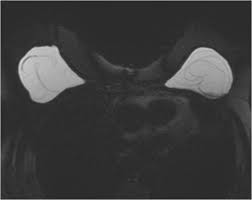

If you have silicone breast implants and suspect that an implant might have ruptured, talk to your plastic surgeon. When a rupture occurs your breast (s) will immediately deflate, usually within a day or two, and breast size will noticeably change. Nevertheless, your body will try to contain any silicone gel seeping in your breast tissue by forming a scar tissue around it, called "granulomas" or "siliconoma". Rupture can also cause capsular contracture. The relationship of free silicone to development or progression of disease is unknown. With silicone gel implants, you aren't able to physically see the appearance of a ruptured implant, whereas with saline implants, you will see a deflated breast with implant rupture. An imaging test, such as an mri or ultrasound, can show whether the implant has ruptured. What are the dangers of silicon? What is the life expectancy of silicone breast implants? Apr 01, 2019 · however, some may remain around the ruptured implant, and this can cause the fluid to change color. What are the risks of silicone implants? Silicone implant rupture that doesn't cause any noticeable symptoms is known as "silent rupture.". This makes is much more difficult to detect a rupture.

What is the life expectancy of silicone breast implants? An imaging test, such as an mri or ultrasound, can show whether the implant has ruptured. The saline will leak from the outer silicone elastomer shell of your implant. Nevertheless, your body will try to contain any silicone gel seeping in your breast tissue by forming a scar tissue around it, called "granulomas" or "siliconoma". Oct 29, 2020 · signs that your silicone implant has ruptured can include changes in breast shape and size, and increasing pain, firmness, and swelling over a period of weeks.

Aug 20, 2020 · pain, soreness or swelling. This makes is much more difficult to detect a rupture. If you have silicone breast implants and suspect that an implant might have ruptured, talk to your plastic surgeon. Nevertheless, your body will try to contain any silicone gel seeping in your breast tissue by forming a scar tissue around it, called "granulomas" or "siliconoma". An imaging test, such as an mri or ultrasound, can show whether the implant has ruptured. Changes in size or shape. What are the risks of silicone implants? What are the dangers of silicon? Silicone implant rupture that doesn't cause any noticeable symptoms is known as "silent rupture.". If you have saline breast implants and experience a rupture, you will immediately be aware of it. When a rupture occurs your breast (s) will immediately deflate, usually within a day or two, and breast size will noticeably change. The saline will leak from the outer silicone elastomer shell of your implant. With silicone gel implants, you aren't able to physically see the appearance of a ruptured implant, whereas with saline implants, you will see a deflated breast with implant rupture.

With silicone gel implants, you aren't able to physically see the appearance of a ruptured implant, whereas with saline implants, you will see a deflated breast with implant rupture. Light, clear fluid usually signals that the ruptured occurred within a month. Nov 14, 2013 · silicone breast implants can leak but do not deflate quickly the way saline implants do because the silicone gel is designed to stay in place when a leak occurs. An imaging test, such as an mri or ultrasound, can show whether the implant has ruptured. Changes in size or shape.